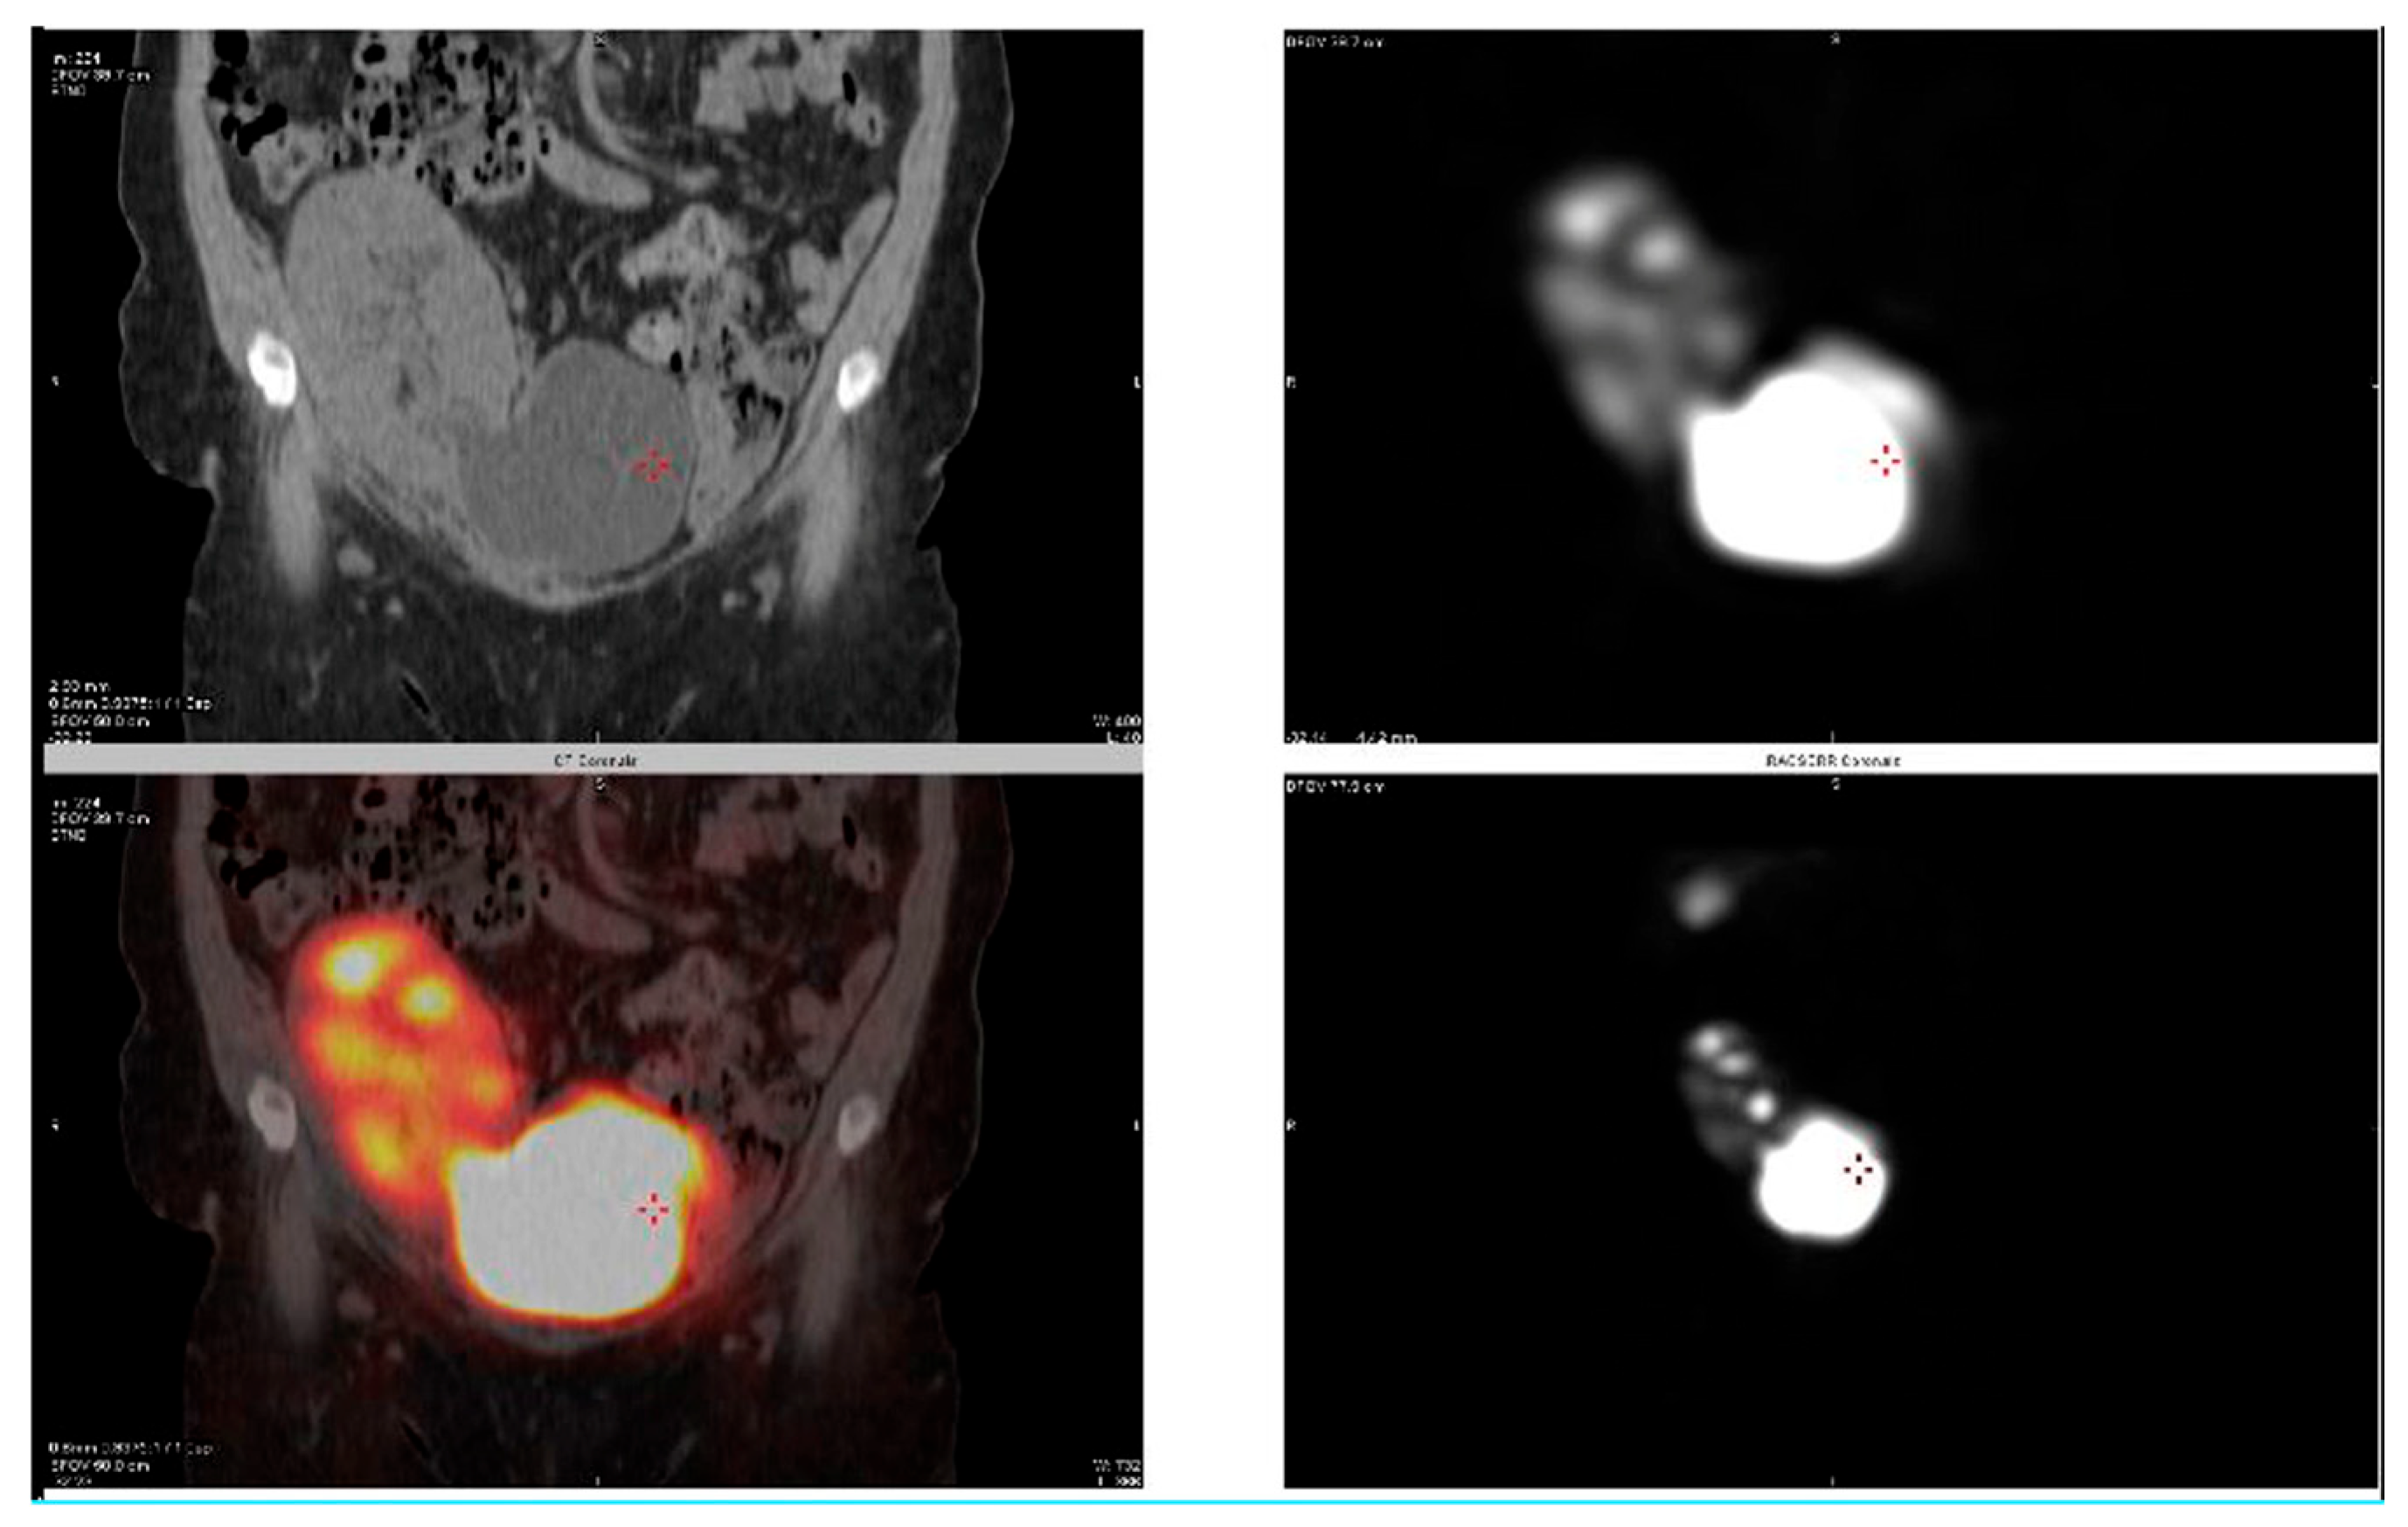

2.2. Case 2